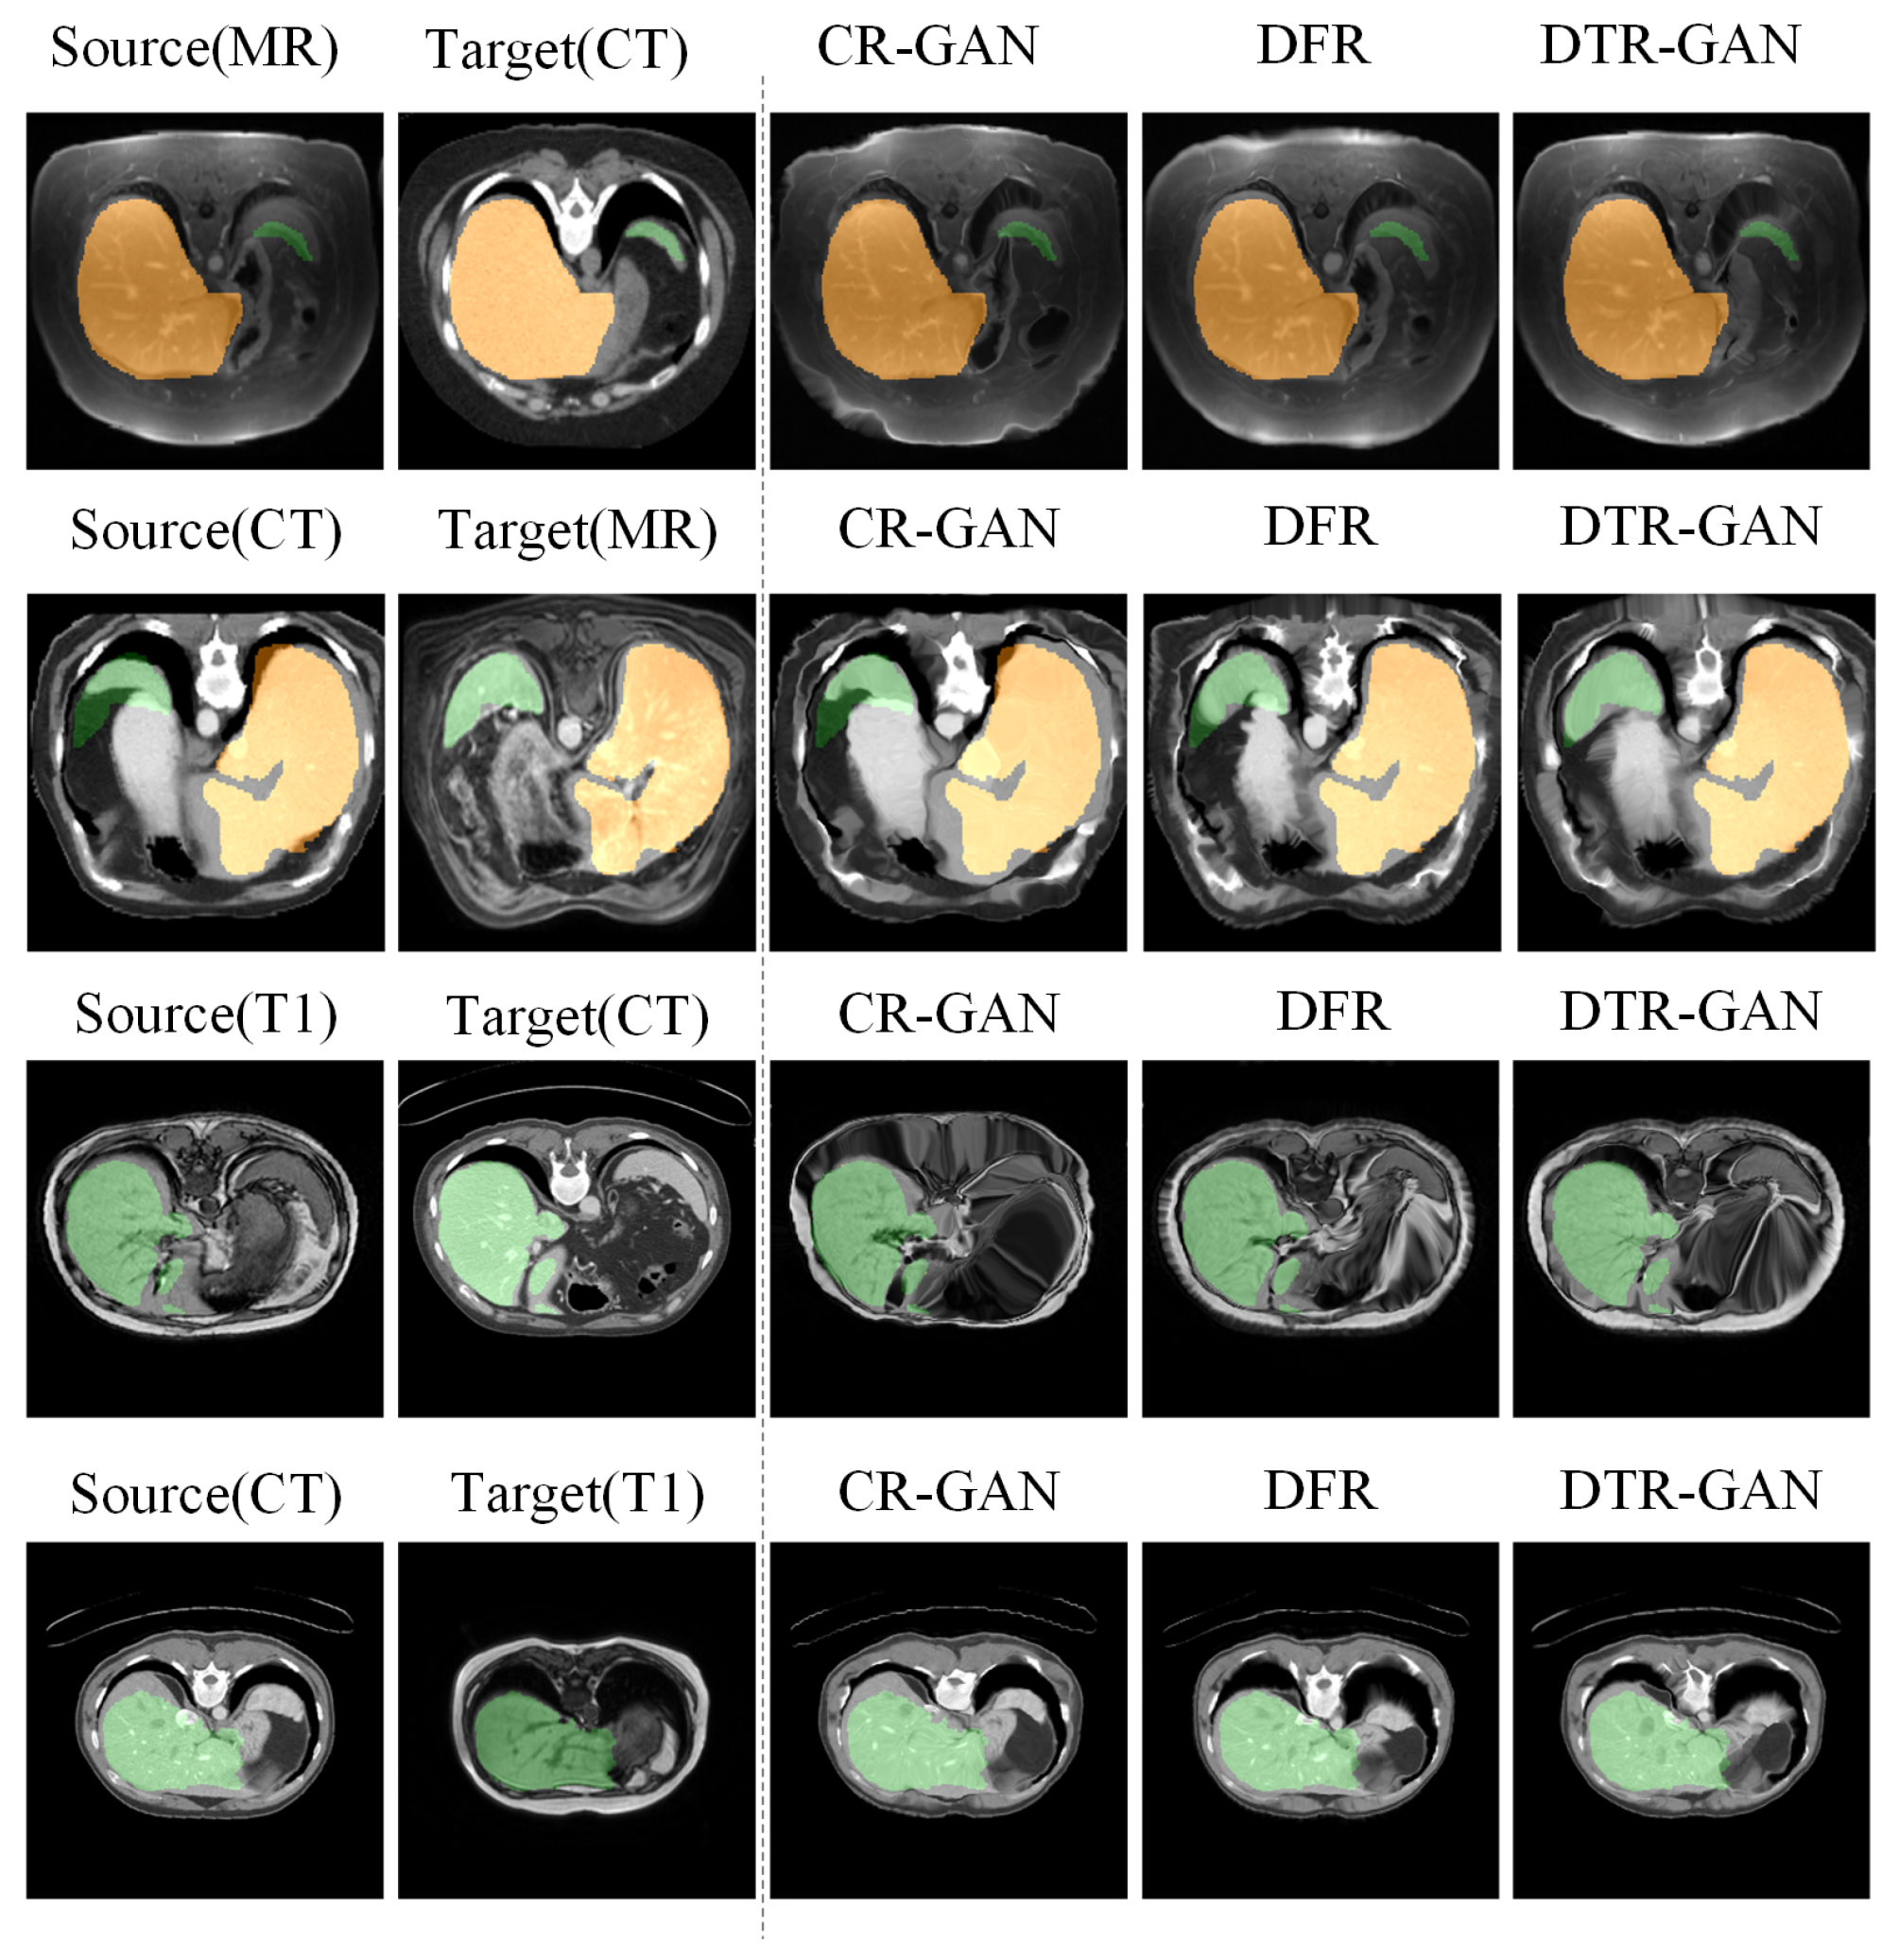

Results on the CHAOS dataset. Table 3 shows the experimental results on the CHAOS dataset. Compared with DFR, the DSC scores of DTR-GAN increased by 1.98% and 1.51% on average in MRI-CT registration and CT-MRI registration, respectively. In addition, the ASD scores of DTR-GAN are decreased by 0.28mm and 0.26mm on average. Figure 6 illustrates the registration results of different methods. Figure 6A,E show warped images, Figure 6B,F show deformation fields, and Figure 6C,D,G,H depict checkerboard grids and overlapping images, respectively, which are visualizations of image alignment effects. As shown in Figure 6, we can observe that the warped image in DTR-GAN is closer to the target image. Figure 6C,G show that the alignment of DTR-GAN is more optimum than the other approaches. The registration results are shown in Figure 7, which shows that our DTR-GAN has a fine registration performance.

Figure 7.

Visual comparison of registration accuracy using various methods is conducted on the Learn2Reg and CHAOS datasets. The first two columns display the original inputs, and all columns show vivid colors to visualize the label.